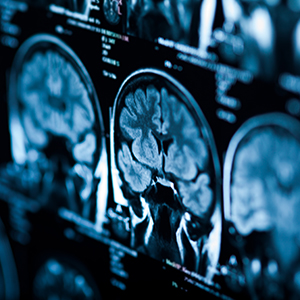

brain scan image

Our team offers a comprehensive Neuro-Oncology Program dedicated to diagnosing and treating brain and spinal cord tumors.